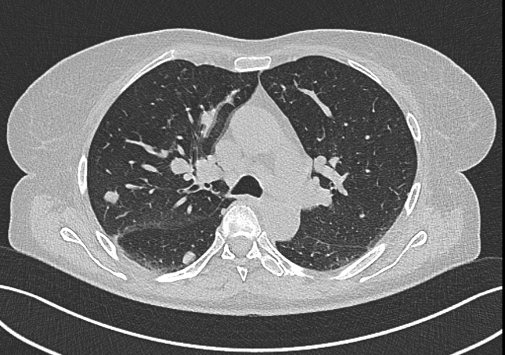

NO: 58letá žena, u níž byla na CT zjištěna objemná vaskularizovaná expanze pravé ledviny 10x12 cm bez trombózy, bez lymfadenopatie. Poté na CT zobrazeny četné plicní metastázy velikosti do 4 cm a metastáza na rozhraní acetabula a kosti kyčelní vpravo. Pod CT kontrolou provedena biopsie nádoru ledviny. Jedná se o tumor pravé ledviny (12 cm) cT2b cN0cM1 (plíce, pravá kyčel).

/ Obr. č. 1-5: CT hrudníku, břicha a pánve, patrná expanze pravé ledviny, plicní metastázy, lytická metastáza v pravé kyčelní kosti.